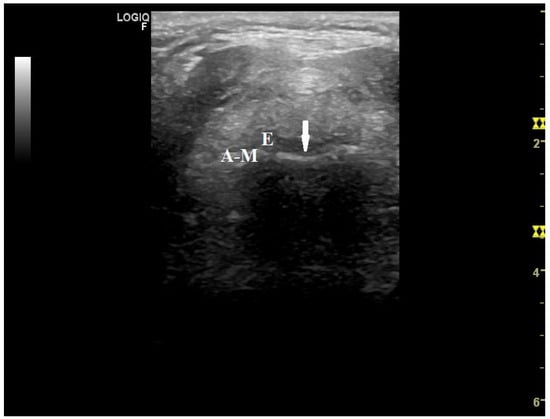

- Brekka, A.K.; Vollsæter, M.; Ntoumenopoulos, G.; Clemm, H.H.; Halvorsen, T.; Røksund, O.D.; Andersen, T.M. Adjustments of non-invasive ventilation and mechanically assisted cough by combining ultrasound imaging of the larynx with transnasal fibre-optic laryngoscopy: A protocol for an experimental study. BMJ Open 2022, 12, e059234. [Google Scholar] [PubMed]

- Andersen, T.; Sandnes, A.; Brekka, A.K.; Hilland, M.; Clemm, H.; Fondenes, O.; Tysnes, O.B.; Heimdal, J.H.; Halvorsen, T.; Vollsæter, M.; et al. Laryngeal response patterns influence the efficacy of mechanical assisted cough in amyotrophic lateral sclerosis. Thorax 2017, 72, 221–229. [Google Scholar] [PubMed]